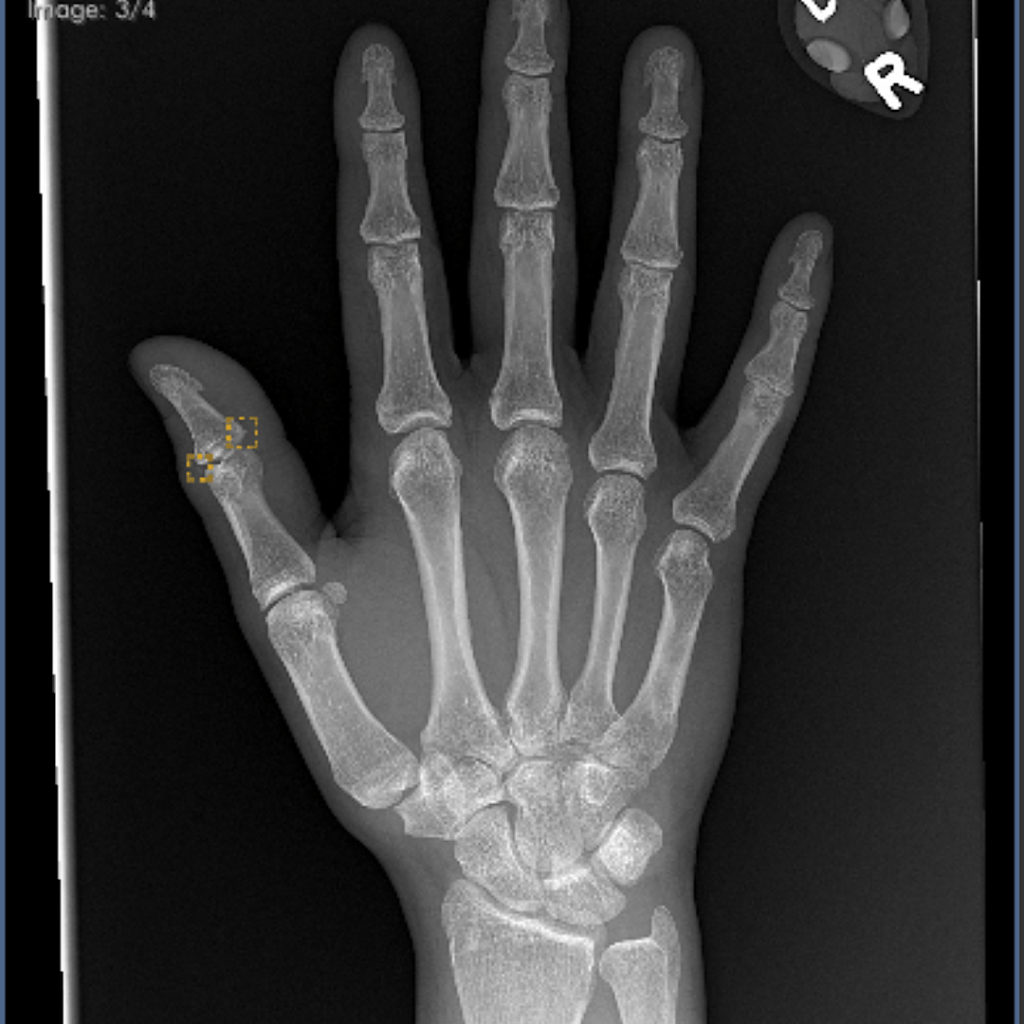

A ten-lead echocardiogram was normal. Thumb shows a possible chip fracture.

But I would like to confirm whether or not it is broken and get a better treatment plan than this huge, cheap splint the ER gave me.